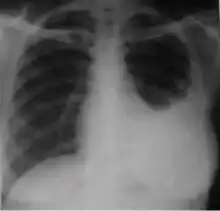

4. Pleural effusion - Presence of a significant amount of fluid within the pleural space. This finding must be distinguished from blunting of the costophrenic angle, which may or may not represent a small amount of fluid within the pleural space (except in children when even minor blunting must be considered a finding that can suggest active TB).

3. Blunting of costophrenic angle (in adults)—Loss of sharpness of one or both costophrenic angles. Blunting can be related to a small amount of fluid in the pleural space or to pleural thickening and, by itself, is a non-specific finding (except in children, when even minor blunting may suggest active TB). In contrast a large pleural effusion, or the presence of a significant amount of fluid in the pleural space, may be a sign of active TB at any age.